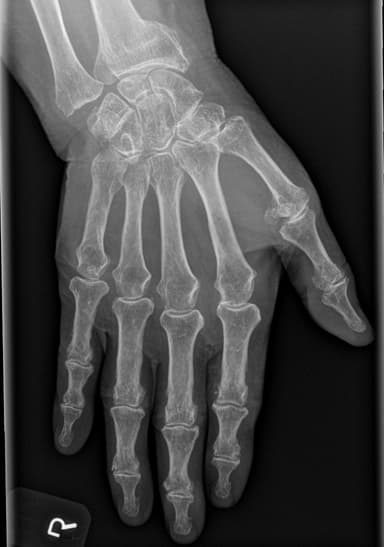

Alignment, frakturmønstre, degenerative forandringer og opfølgende sammenligning.